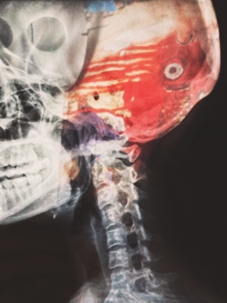

xray of skull

A traumatic brain injury (“TBI”) is one of the most devastating potential consequences of a personal injury accident. Many people are never the same again after suffering this injury. If someone else was to blame for your traumatic brain injury, or the one suffered by a family member, you might be entitled to significant financial compensation. First, an attorney would need to prove that someone should be legally responsible for your injury.